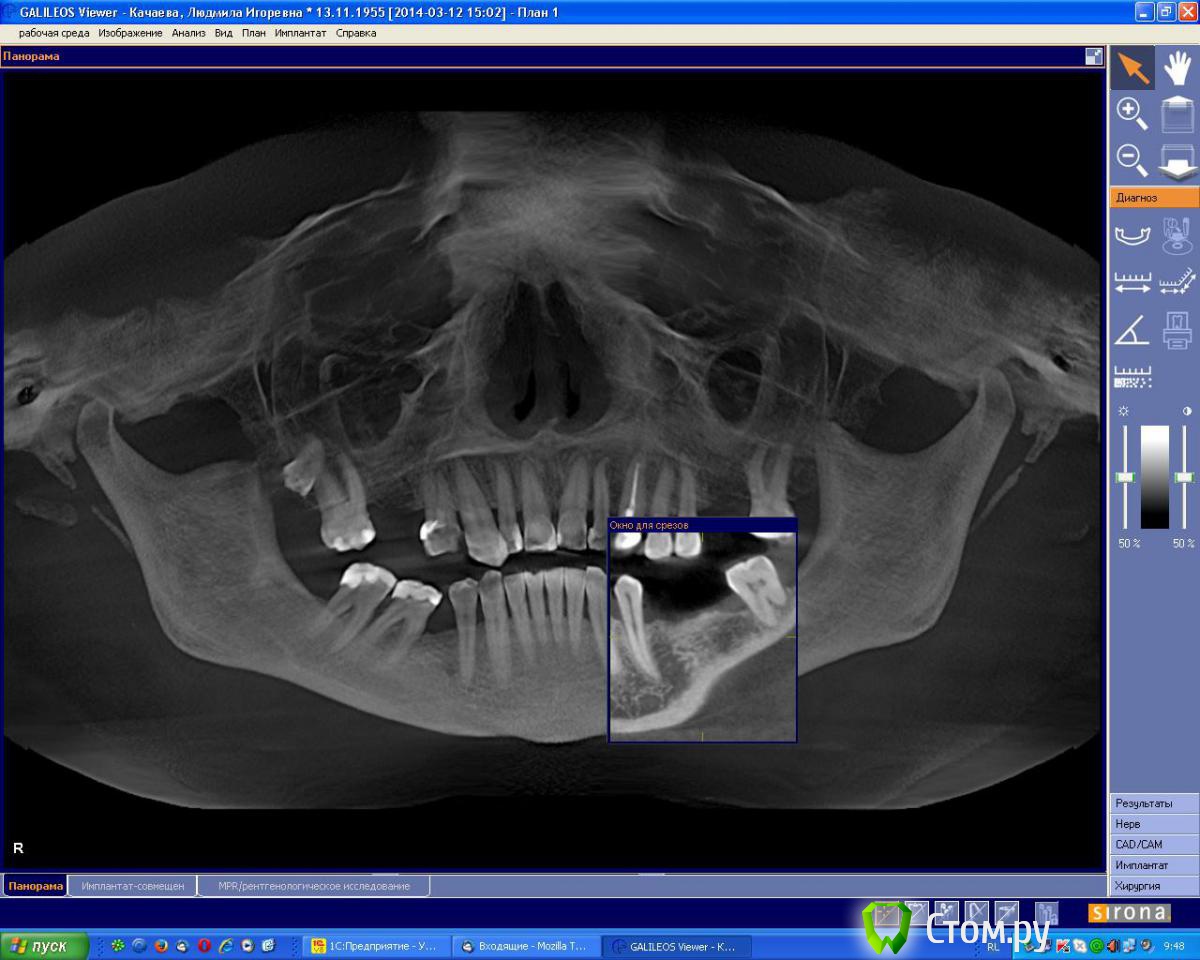

an_ver Опубликовано 7 августа, 2014 Поделиться Опубликовано 7 августа, 2014 Планируется установка 2 имплантов в обл.35,37 по высоте проходит,по толщине нет.Предпочтительный метод в данной ситуации? Ссылка на комментарий